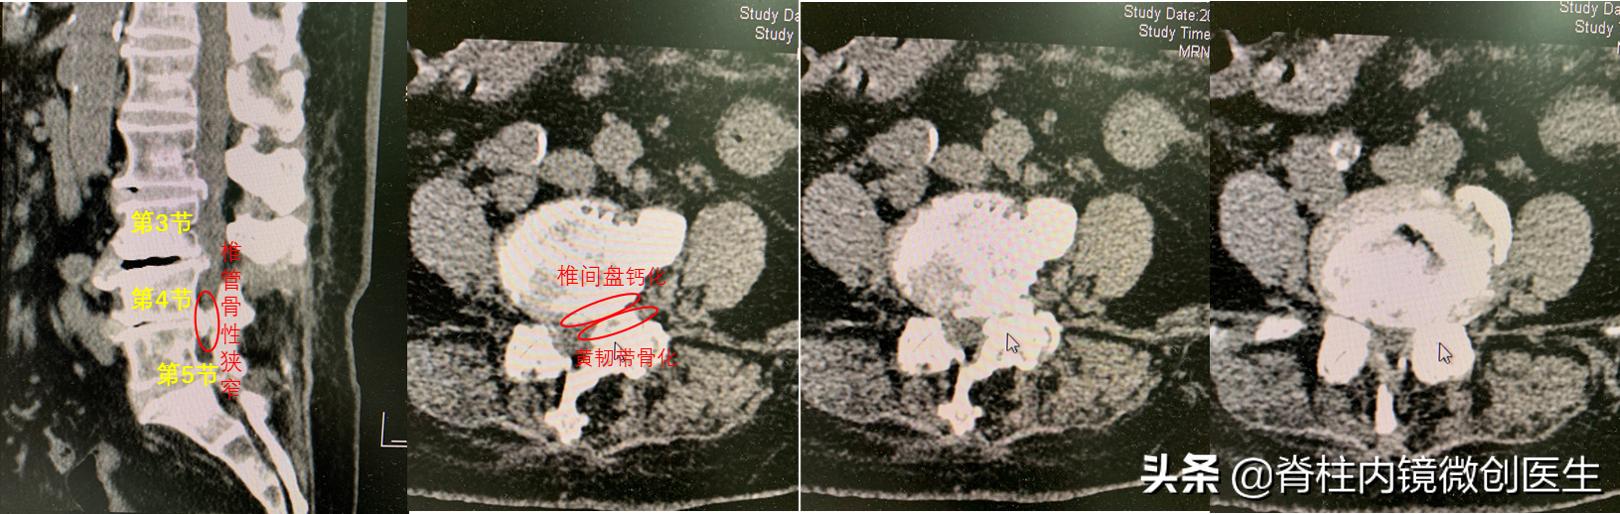

【影像学 - 腰椎CT】可见腰3-4和腰4-5椎体后缘均有骨赘,且腰4-5骨赘最为明显,合并后方黄韧带增厚骨化,提示腰4-5节段是最主要节段。

腰椎疾病CT检查可以提示是否有钙化或者骨化,为手术提供重要参考